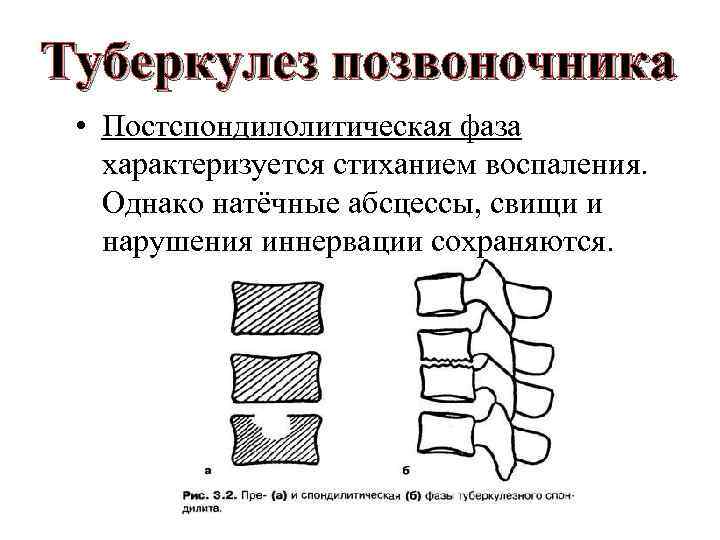

Туберкулез позвоночника • Постспондилолитическая фаза характеризуется стиханием воспаления. Однако натёчные абсцессы, свищи и нарушения иннервации сохраняются.

Туберкулез позвоночника • Постспондилолитическая фаза характеризуется стиханием воспаления. Однако натёчные абсцессы, свищи и нарушения иннервации сохраняются.